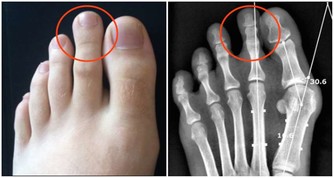

便秘造成的憩室,是大腸藏汙納垢的溫床

有些人在用力排便時,腸子因為壓力的關係,

讓結腸壁較脆弱的地方像吹氣球一樣

長出一個氣囊出來,就形成了憩室。

它是一種良性的囊袋,是大腸最容易藏汙納垢的地方,

如果不處理,久而久之就有形成大腸癌的可能。

憩室一旦長出來就不易消除,

老人家和便秘者有百分之三十到四十的人都會有憩室,

平時不痛不癢,就像盲腸一樣,

如果沒有髒東西跑進去就沒事,

但如果排泄物囤積其中,就容易發生感染或發炎。

因此,已經有憩室的人應以斷食、灌腸

來定期清除裡面的髒東西。